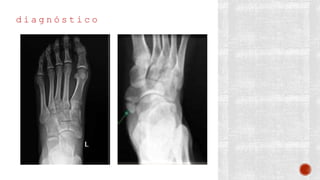

d i a g n ó s t i c o

¬ Clínico

¬ Radiográfico

- AP de pie

- Lateral de pie

- Axial de Harris

- De Broden

- Transversa

- TAC